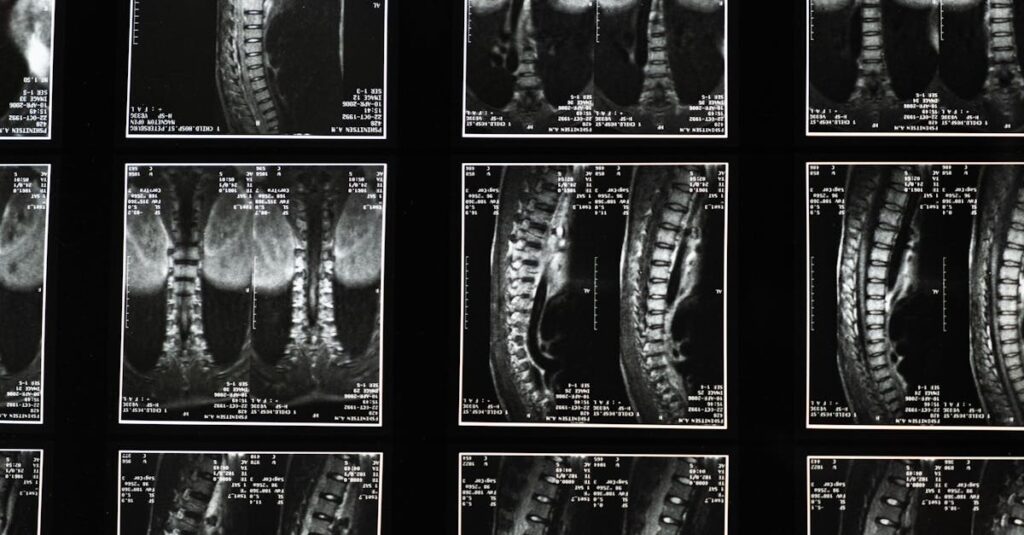

Quels examens permettent de diagnostiquer un bombement discal?

Une IRM ou une radiographie sont les outils les plus couramment utilisés pour diagnostiquer un bombement discal.